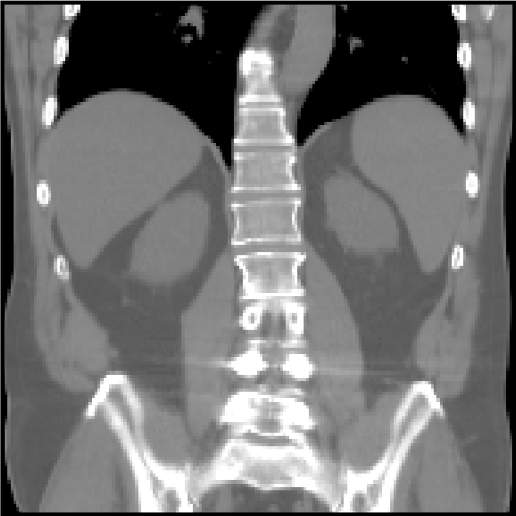

Abdomen MR-CT OASIS Lung CT

Fixed Moving Fixed Moving Fixed Moving

[Uncaptioned image] [Uncaptioned image] [Uncaptioned image] [Uncaptioned image] [Uncaptioned image] [Uncaptioned image]

Modalities MR T1w / CT MR T1w / MR T1w CT / CT

Intra-/Inter-patient Intra-patient Inter-patient Intra-patient

Resolution 192×160×192192160192192{\times}160{\times}192 160×192×224160192224160{\times}192{\times}224 192×192×208192192208192{\times}192{\times}208

Voxel size 2×2×2 mm222timesabsentmillimeter2{\times}2{\times}2$\text{\,}\mathrm{mm}$ 1×1×1 mm111timesabsentmillimeter1{\times}1{\times}1$\text{\,}\mathrm{mm}$ 1.75×1.25×1.75 mm1.751.251.75timesabsentmillimeter1.75{\times}1.25{\times}1.75$\text{\,}\mathrm{mm}$

Cases (Train/Test) 8/8 416/39 20/10

Preprocessing canonical affine pre-align affine pre-align

crop/pad/resample crop/pad/resample

Annotations (Train/Test) 4/9 anatomical labels 35/35 anatomical labels –/100 landmarks/case

Additional data 90 unpaired MR/CT scans lung masks

ROI masks

Metrics DSC/DSC9/HD95 DSC/DSC30/HD95 TRE/TRE30

SDlogJ/RT SDlogJ/RT SDlogJ/RT

Challenges \mathbin{\vbox{\hbox{\scalebox{2.5}{$\bullet$}}}}\mathbin{\vbox{\hbox{\scalebox{2.5}{$\bullet$}}}}\mathbin{\vbox{\hbox{\scalebox{2.5}{$\bullet$}}}}\mathbin{\vbox{\hbox{\scalebox{2.5}{$\bullet$}}}}\mathbin{\vbox{\hbox{\scalebox{2.5}{$\bullet$}}}}\mathbin{\vbox{\hbox{\scalebox{2.5}{$\bullet$}}}}\mathbin{\vbox{\hbox{\scalebox{2.5}{$\bullet$}}}} \mathbin{\vbox{\hbox{\scalebox{2.5}{$\bullet$}}}}\mathbin{\vbox{\hbox{\scalebox{2.5}{$\bullet$}}}} \mathbin{\vbox{\hbox{\scalebox{2.5}{$\bullet$}}}}\mathbin{\vbox{\hbox{\scalebox{2.5}{$\bullet$}}}}\mathbin{\vbox{\hbox{\scalebox{2.5}{$\bullet$}}}}\mathbin{\vbox{\hbox{\scalebox{2.5}{$\bullet$}}}}\mathbin{\vbox{\hbox{\scalebox{2.5}{$\bullet$}}}}\mathbin{\vbox{\hbox{\scalebox{2.5}{$\bullet$}}}}

TABLE I: Overview of all six Learn2Reg tasks addressing the imminent challenges of medical image registration: multi-modal scans \mathbin{\vbox{\hbox{\scalebox{2.0}{$\bullet$}}}} (tasks with at least two different image modalities), few/noisy annotations \mathbin{\vbox{\hbox{\scalebox{2.0}{$\bullet$}}}} (less than five annotated anatomical structures for training cases), partial visibility \mathbin{\vbox{\hbox{\scalebox{2.0}{$\bullet$}}}} (restricted or cropped field of view for at least one image of a registration pair), small datasets \mathbin{\vbox{\hbox{\scalebox{2.0}{$\bullet$}}}} (less than 30 training cases), large deformations \mathbin{\vbox{\hbox{\scalebox{2.0}{$\bullet$}}}} (tasks with initial displacements of at least 10 cm10timesabsentcentimeter10$\text{\,}\mathrm{cm}$), small structures \mathbin{\vbox{\hbox{\scalebox{2.0}{$\bullet$}}}} (tasks containing cases with target structures comprising less than 100 voxels), unsupervised registration \mathbin{\vbox{\hbox{\scalebox{2.0}{$\bullet$}}}} (no annotations for training cases) and missing correspondences \mathbin{\vbox{\hbox{\scalebox{2.0}{$\bullet$}}}} (e.g. due to removed organs, different field of views etc.)

.

Abdomen MR-CT

The data was compiled from public studies of the cancer imaging archive (TCIA) [23] that contained paired scans of both MR and CT from the same patients. In particular, 16 MR and CT scans from the following studies, TCGA-KIRC [24], TCGA-KIRP [25], and TCGA-LIHC [26], are included in Learn2Reg - that cover routine diagnostic scans and follow-up imaging for kidney surgery. The data has been resampled to an isotropic resolution of 2mm, and cropped and padded to achieve voxel dimensions of 192x160x192. We have also manually traced 3D segmentation masks for the liver, spleen, left and right kidney. All scans were pre-aligned using a groupwise affine registration based on the deeds-linear algorithm [27]. Additional unpaired and segmented training data from two further challenges - BCV-CT [12] and CHAOS-MR [28, 29] - were provided for pre-training.